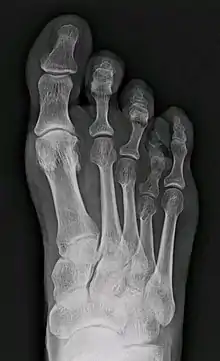

| X-ray of congenital brachymetatarsia involving fourth metatarsal bone | |

Brachymetatarsia is a rare malformation that causes one or more toes to be abnormally short. The condition is characterized by a metatarsal arch shortness of more than 5 mm. The condition is more common in females, and the incidence reported in the literature ranges from 0.02% to 0.05%. Brachymetatarsia appears to be the result of epiphyseal plate retardation or premature closure. The etiology may be congenital and idiopathic, posttraumatic, postinfection, iatrogenic, or secondary to a systemic disease such as cancer, sickle cell disease, pseudohyperparathyroidism, Turner's syndrome, Down's syndrome, Apert syndrome, athyroidism, or osteodystrophy.[2]

It most frequently involves the fourth metatarsal. If it involves the first metatarsal, the condition is known as Morton's syndrome. Treatment is via a number of differing surgical procedures.[3]